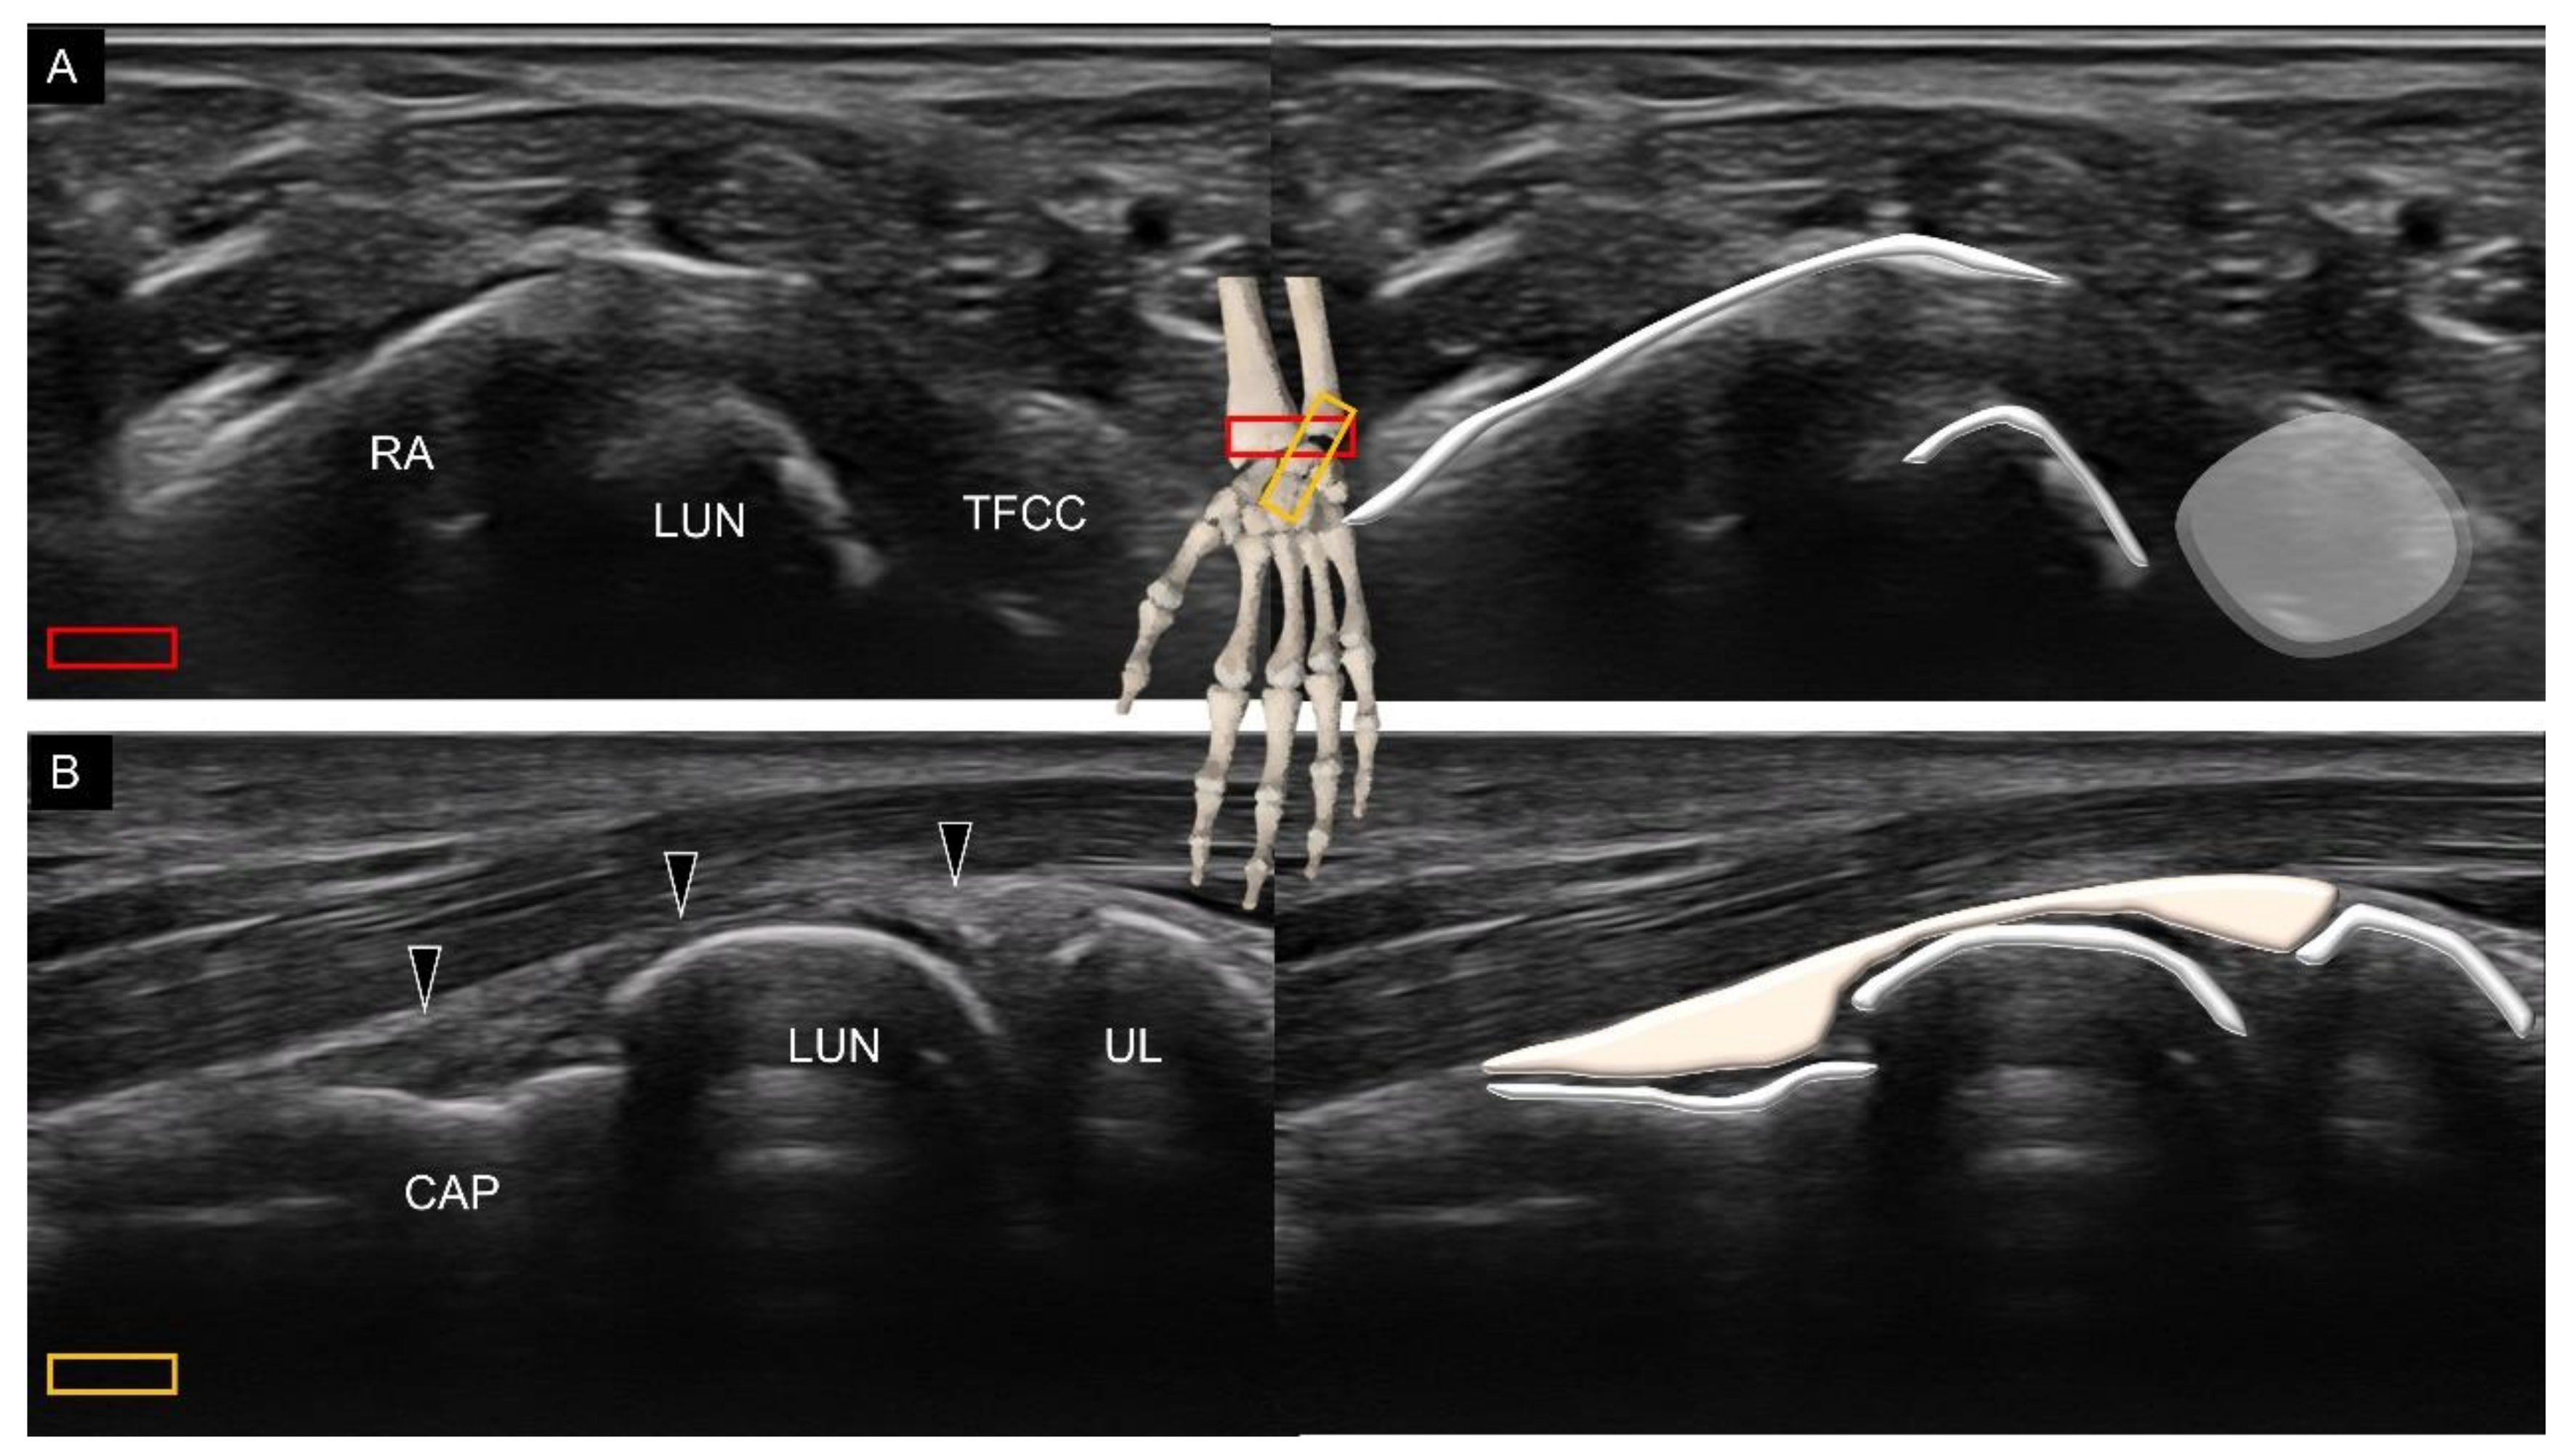

3.2. Attachment to the Lunate

3.3. Attachment to the Triquetrum

4. Sonoanatomy of Volar Intrinsic Carpal Ligaments